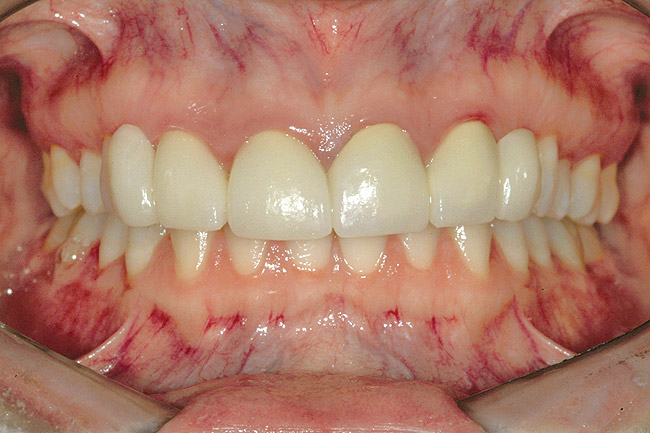

Fig 6 (and Fig 7). Prerestorative orthodontics was completed in 5 months. Final result 3 years, 4 months after completion.

Figure 6

Fig 7 (and Fig 6). Prerestorative orthodontics was completed in 5 months. Final result 3 years, 4 months after completion.

Figure 7

Fig 8 (and Fig 9). Teeth Nos. 5 and 12 were converted to Nos. 6 and 11, and Nos. 6 and 11 were converted to Nos. 7 and 10. Nos. 4 and 13 were enlarged. Note stability and absence of orthodontic relapse. Before-and-after smiles. Periodontist: Edward P. Allen, DDS, PhD. Prosthodontist: Robert R. Winter, DDS.

Figure 8

Fig 9 (and Fig 8). Teeth Nos. 5 and 12 were converted to Nos. 6 and 11, and Nos. 6 and 11 were converted to Nos. 7 and 10. Nos. 4 and 13 were enlarged. Note stability and absence of orthodontic relapse. Before-and-after smiles. Periodontist: Edward P. Allen, DDS, PhD. Prosthodontist: Robert R. Winter, DDS.

Figure 9